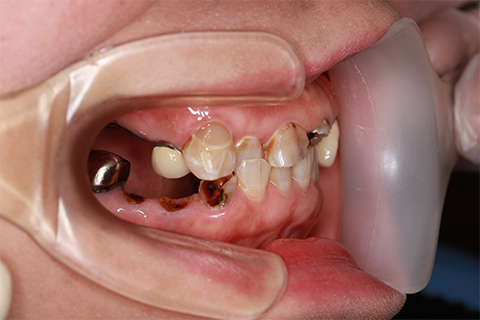

症例5

治療前

インプラント埋入時

治療後

- 年齢・性別

- 35歳男性

- 治療期間

- 3ヶ月

- 抜歯

- 右上1.3左上6.7の残根抜歯

- 治療費

- 123.2万円

- 備考

- 右上1.3左上6.7の欠損部

- 治療内容

- 4本のインプラントを一回のオペで埋入。

- 施術の副作用(リスク)

- オペによる知覚障害。インプラントによる歯肉炎。インプラント脱落。